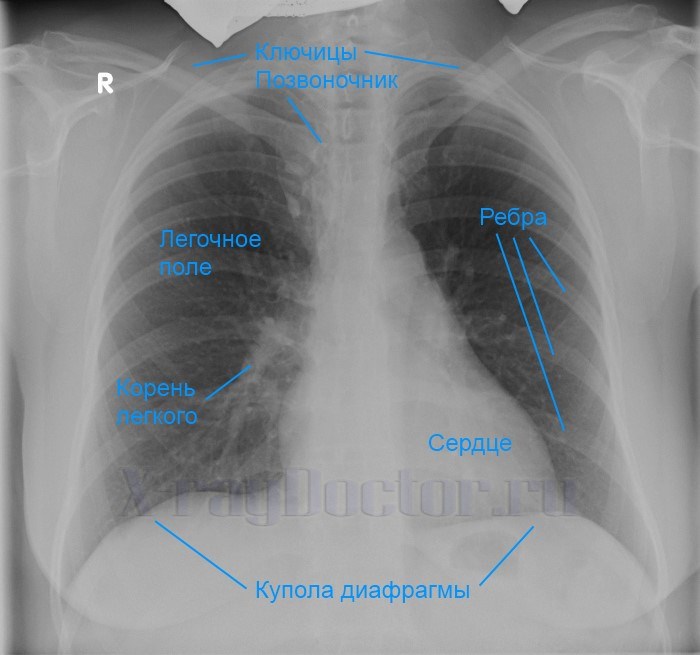

Нормальная рентгенограмма легких: что нужно знать

Раздел: Мудрость в объективе